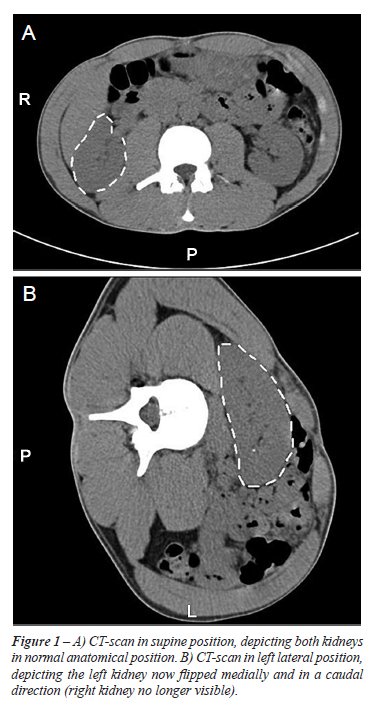

scan showed a mobile right kidney, Figure-1. None of the patients had

any previous history of urinary tract infections, hypertension or renal

calculi. Patient characteristics are given in Table-1.

move freely in a caudal and medial direction (Figure-1). We therefore